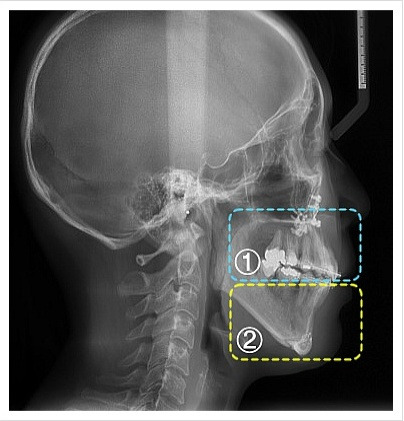

삼악수술은 턱의 세 가지 주요 부위를 동시에 교정하는 수술입니다. 일반적으로 돌출입과 하악왜소증을 동시에 개선하기 위해 시행됩니다. 이 수술은 턱의 위치를 조정하고, 교합을 개선하여 기능적인 문제를 해결하는 데 중점을 둡니다.

삼악수술의 전후 비교

수술 전에는 턱의 비대칭이나 돌출입으로 인해 고민했던 많은 사람들이 수술 후에는 이러한 문제들이 해소되어 자신감이 높아지는 모습을 보입니다.

수술 전후의 사진을 비교해 보면 얼굴의 형태가 얼마나 달라졌는지를 쉽게 확인할 수 있습니다.